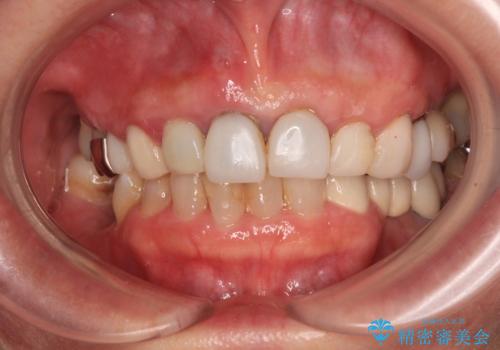

周辺の歯は20年以上前に装着したクラウンで、色合いや形態が気になっているとのことで、オールセラミックブリッジにて補綴治療を行うこととしました。

まずは土台の歯を引っぱり出し、外科処置により歯肉の状態を十分に整えた上で、オールセラミッククラウンにて補綴することとしました。

元々の土台は歯肉の中に埋もれており、歯肉が著しく腫れている状態だったため、歯を引っぱり出すこととしました。引っぱる期間は2ヶ月ほどで済み、その後歯周外科処置を行ったことで、土台周りの歯肉は腫脹のない健全な状態へと改善されました。